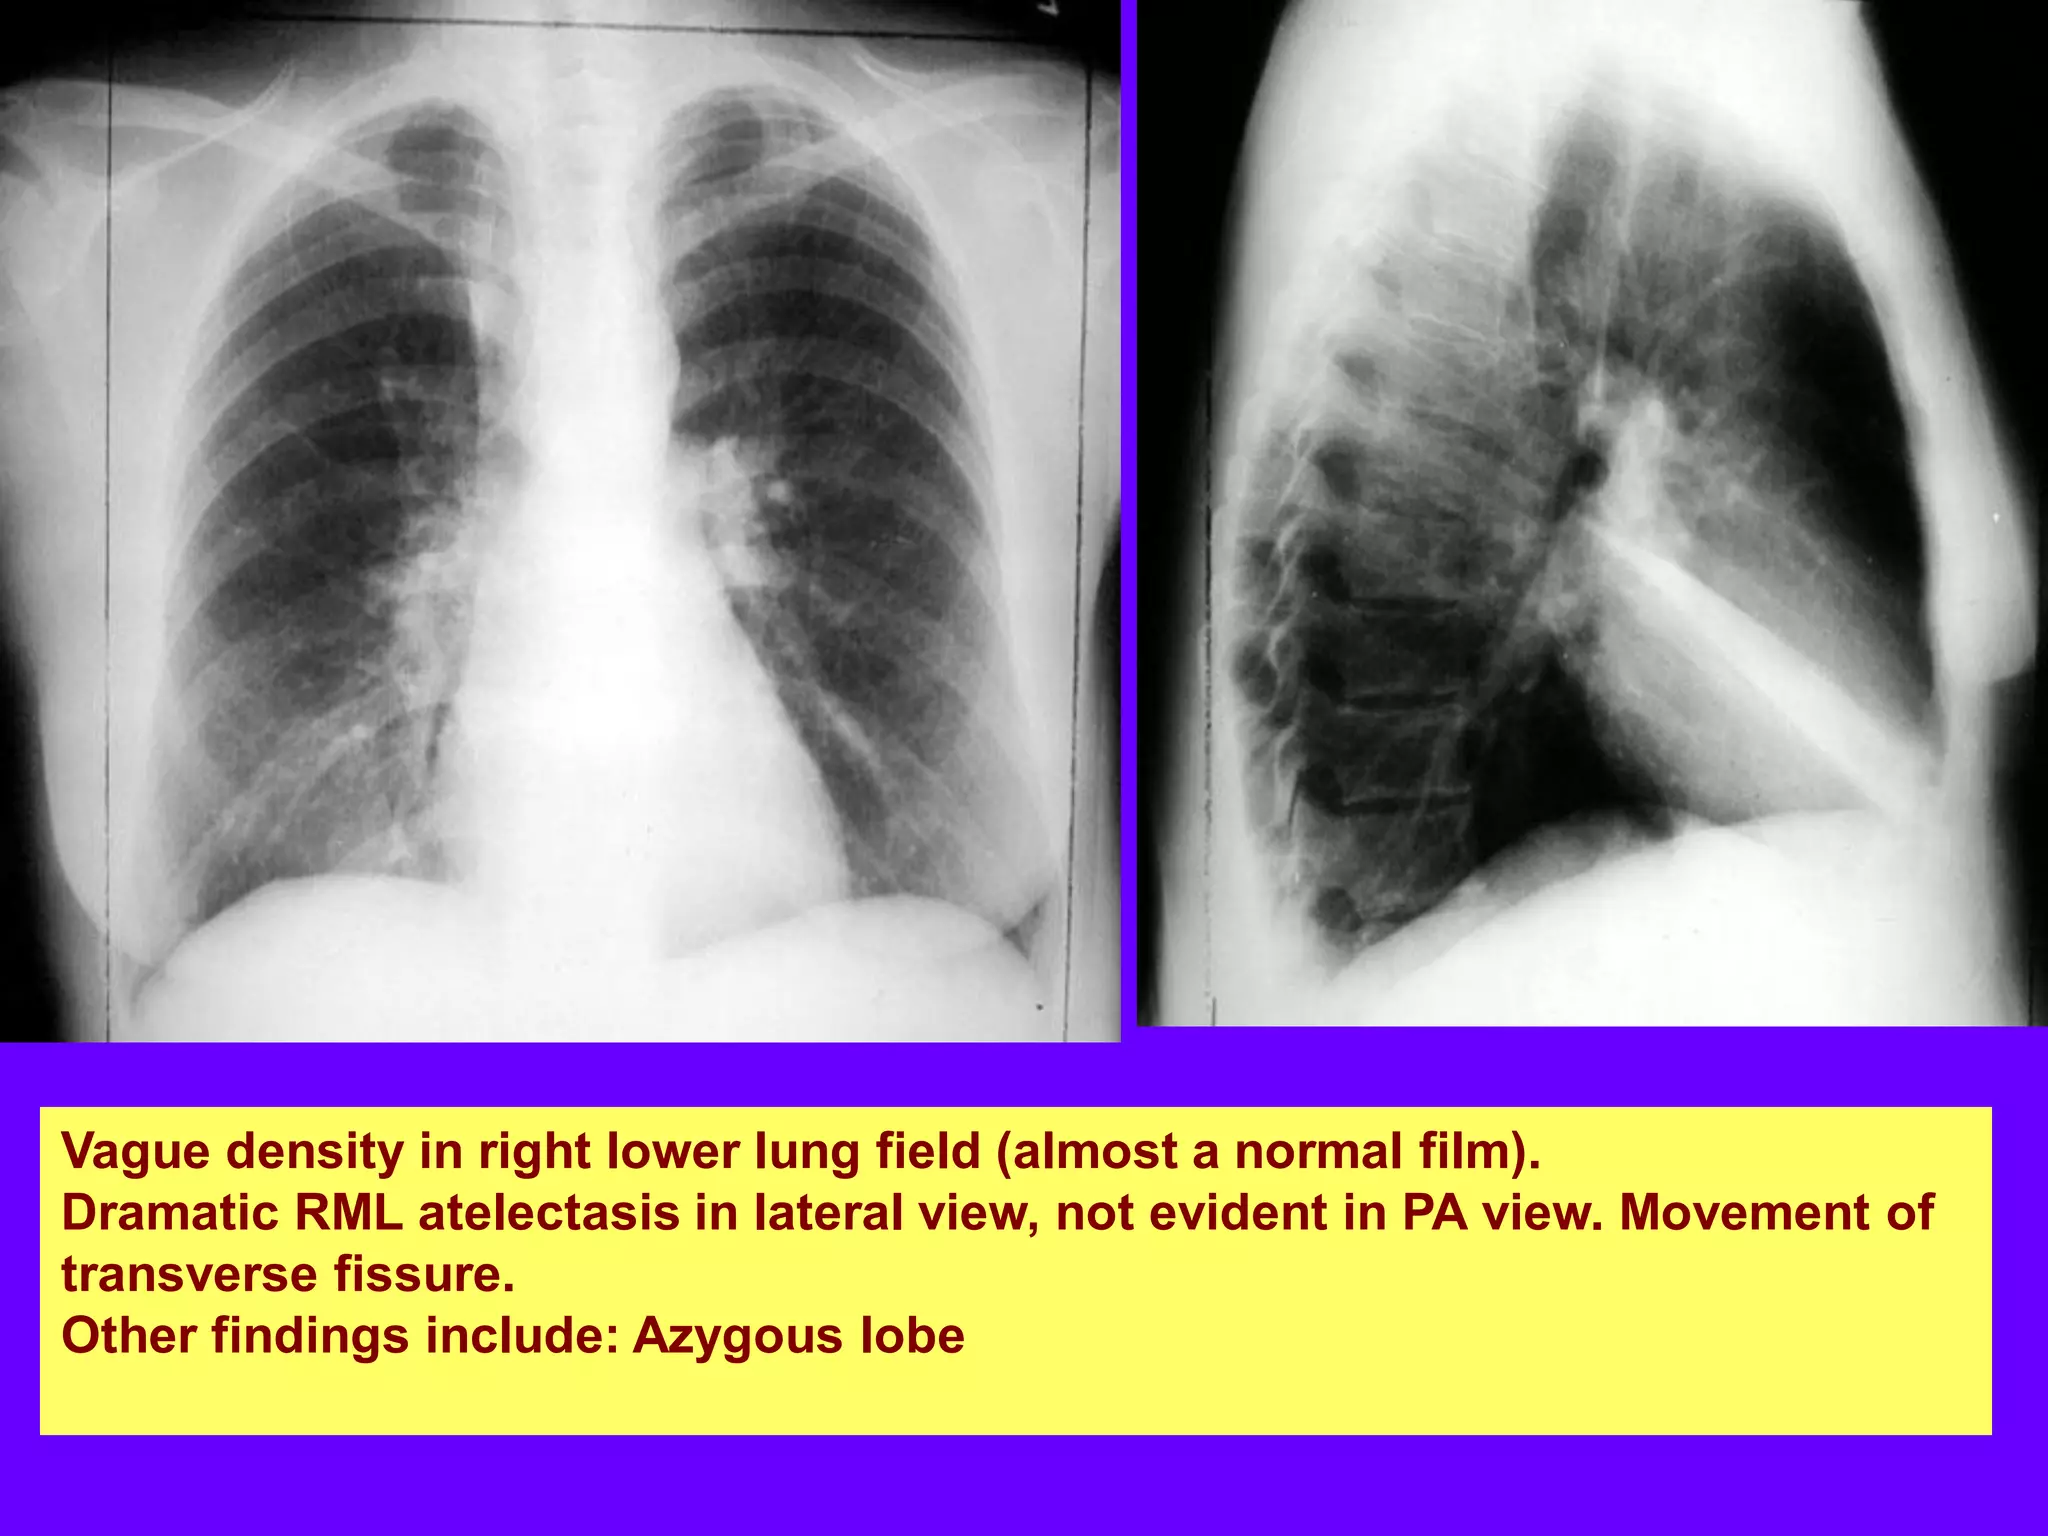

RML Atelectasis

Vague density in right lower lung field, almost normal

RML atelectasis in lateral view, not evident in PA view

Vague density in right lower lung field (almost a normal film).

Dramatic RML atelectasis in lateral view, not evident in PA view. Movement of

transverse fissure.

Other findings include: Azygous lobe